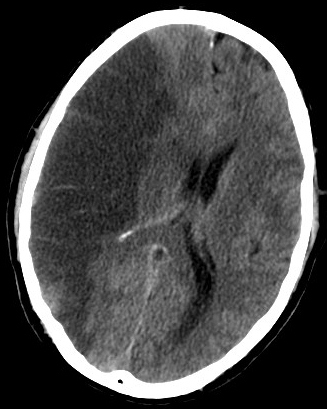

Intracerebral Hemorrhage

An intracerebral hemorrhage is due to brain parenchyma bleeding.

Intracerebral hemorrhage may result from:

- Lenticulostriate vessel rupture

- Aneurysm rupture

The most typical location of the brain involved by intracerebral hemorrhage is the basal ganglia.

Intracerebral hemorrhage hemorrhages may be caused by hypertension.

Hypertension treatment decreases the risk of intracerebral hemorrhage by half.